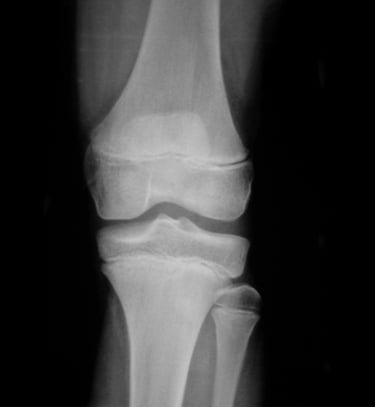

Gydytojas Markas Fiodorovas - ortopedas traumatologas, sporto traumų specialistas, sukaupęs 20 metų patirtį tausojančioje artroskopinėje chirurgijoje. Daugiau nei 650 artroskopinių kelio, peties ir kitų sąnarių operacijų per metus atliekantis chirurgas, taip pat aktyviai įsitraukęs į mokslinę veiklą. Gydytojas yra nuolatinis tarptautinių konferencijų lektorius bei tarptautinis artroskopinės chirurgijos instruktorius.